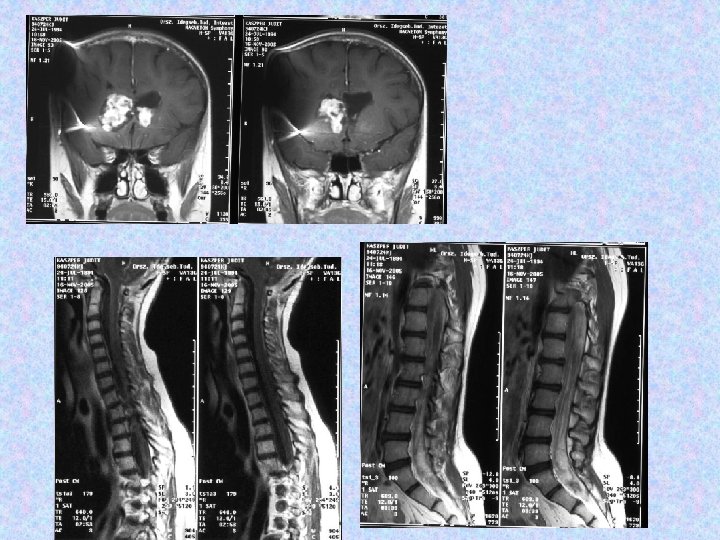

• MR vizsgálat készült liquorpassage zavar miatt. • MR vizsgálat meningeális kontraszthalmozást mutatott a bazális ciszterna, a cerebri media, a ciszterna magna területében. • Felmerült a meningitis basilaris gyanúja, amely nem igazolódott. • Liquor fehérje: 7, 05 g/l, glükóz: 5, 0 mmol/l, sejtszám 10/látótér. Baktérium nem tenyészett ki. Mikrobiológia, szerológia negatív. Citológia gyulladásos szedimentációt véleményezett. Tumor sejtek nem voltak láthatóak. • Spinalis MR thoracalis compressziót, meningeális szóródást mutatott.

• 2002. július 10 -én koponya és teljes gerinc MRI felvétel történt. A koponya MRI felvételek összevetve a 2001. június 27 -i felvételekkel aszimmetrikus kamrarendszert mutattak, a bal kamra kitágulásával. A jobb kamra szűk, a shunt vége a frontális szarv dorzális részében helyezkedik el, jól működik. A harmadik kamra területén egy intenzíven halmozó terime látható, továbbá bal kamraszarvban bazálisan. A szubarachnoideális liquorterek megtartottak, kóros halmozás nem figyelhető meg. • A gerinc MR felvételen a kraniocervikális átmenetben, a nyúltvelő ventrális felszínén sáv alakú halmozást írtak le. Th. VII-VIII. , L. I-II. csigolyákban, a conus körül szolid halmozás figyelhető meg. Az alacsonyabb thoracalis szakaszokon lévő myelon felszínén és intradurálisan homogén halmozást írtak le. • A neuro-onkológiai konzílium nem javasolt további kemo- és radioterápiát.

• A 2006. szeptember 27 -i MRI összevetve a 2005. november 16 -i MRI-vel: a halmozás amorf formájú növekvő tumor masszát mutat mindkét frontális kamraszarvban. A kamrarendszer továbbra is tág. A caudalis durazsák halmozó tumor masszával kitöltött.

• A következő műtét 2006. októberében történt. Részleges eltávolítás, aqueductoplasica történt. Szövettan pilocitás asztrocitómát igazolt. • 2006. 12. 16 -án készült MR vizsgálat kiterjedt intraventriculáris, subarachnoideális, thoracolumbális halmozási többletekkel járó teljes neuraxist érintő disszeminációt ábrázolt.

• Progrediáló járászavar, bal oldali alsóvégtagi fájdalom miatt megismételt MR vizsgálat L. I. szintben igazolt myeloncompressiót okozó növekedést az egyebekben változatlan szóródás mellett. 2007. 01. 19 -i műtét során parciális eltávolítás történt, objektivizált teljes tumorszóródás mellett.